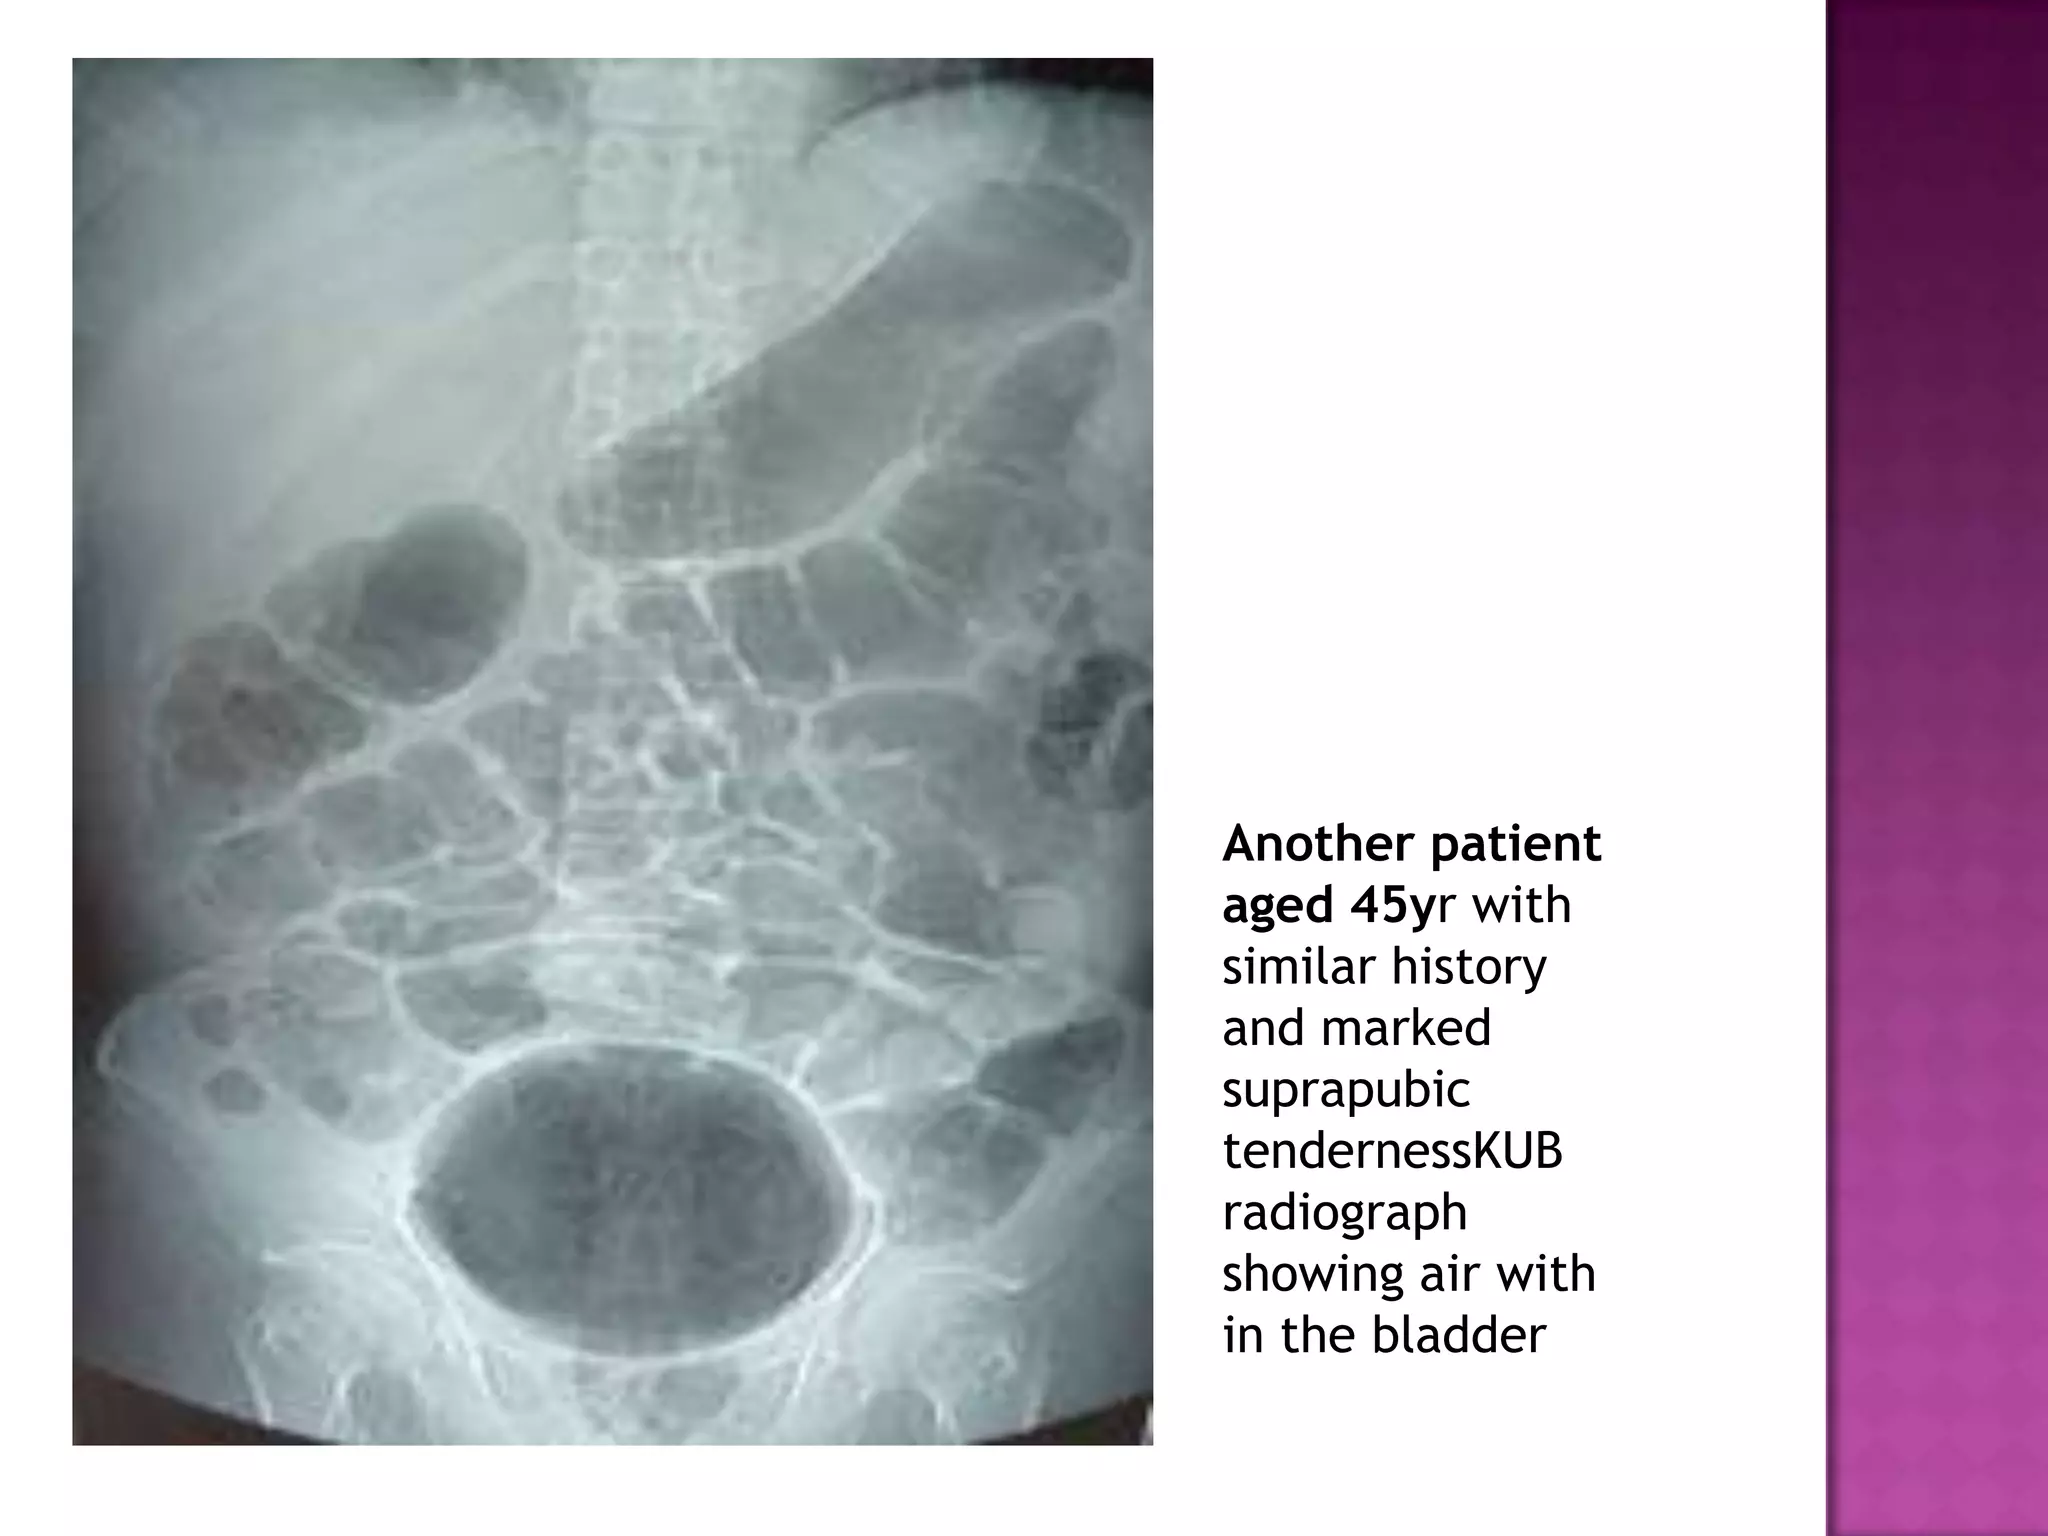

Another patient

aged 45yr with

similar history

and marked

suprapubic

tendernessKUB

radiograph

showing air with

in the bladder